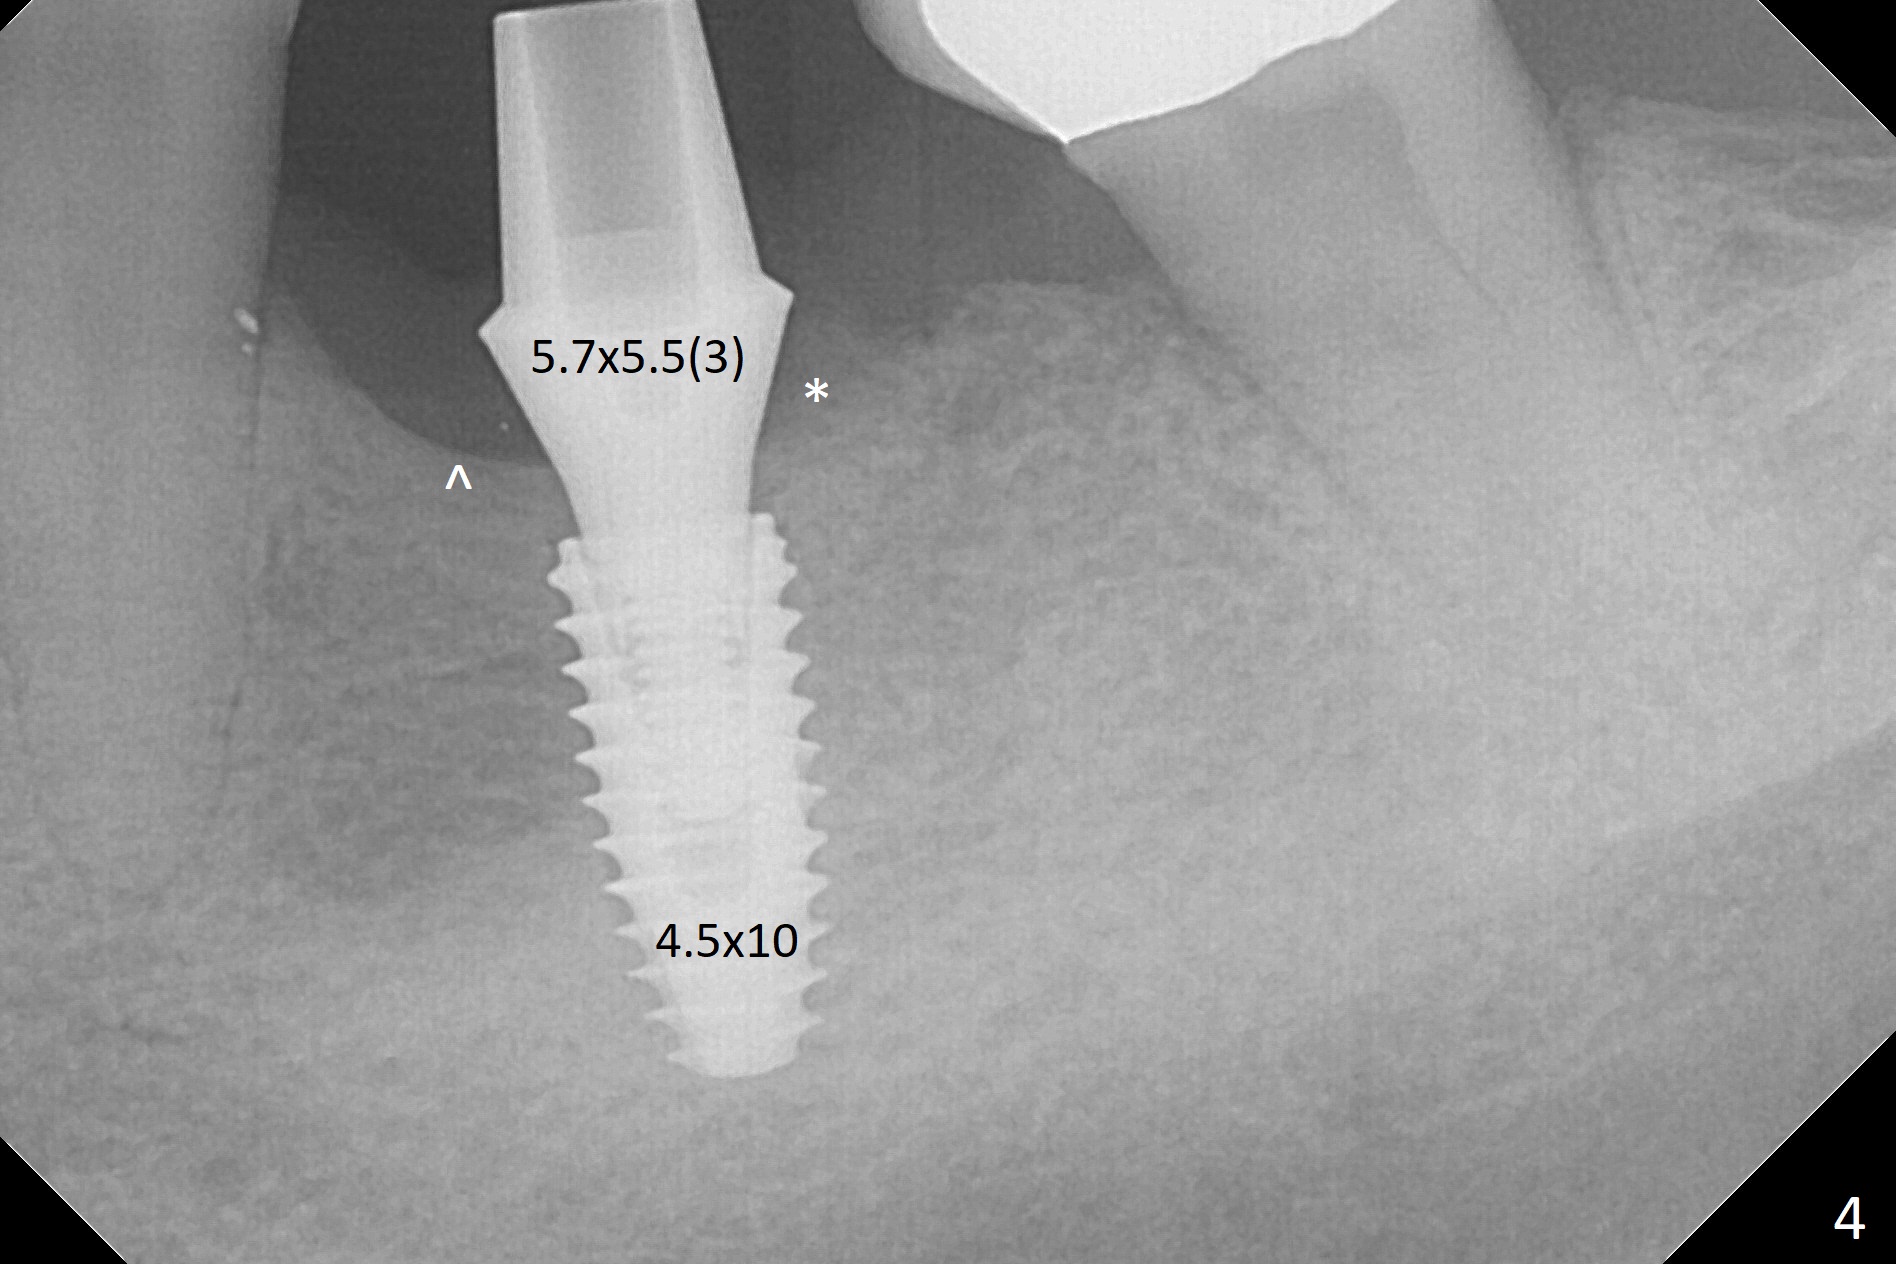

After extraction of the distal residual root at #19 (Fig.1), osteotomy is initiated in the mesial (M) aspect of the distal socket (Fig.2). Magic Split proves dense bone. When a 4.5x10 mm dummy implant is placed with stability, there is an apical space (Fig.3 <); the dummy abutment is 5.7x5.5(2). With the final implant (4.5x10 mm, Fig.4) being placed deeper to close the apical space, the cuff of the final abutment increases by 1 mm. Autogenous bone is used to pack around the implant distobuccally (*). Although the implant seems to be placed significantly apical to the lingual crest (^), it is at the buccal crest. There seems to be no bone loss 3 months postop; impression is taken (Fig.5). The crown/abutment at #30 is retightened 22 days post cementation (5 months postop), probably related to unilateral mastication. In fact, #30 is the only functioning molar on the right side (with unfavorable crown/implant ratio (long cuff 4 mm, vs. 3 mm at #19); #2 severely decayed); the crown at #19 is cemented at the same appointment (Fig.6). The crowns/abutments at #19 and 30 are loose 7 months later. When the crown/abutment at #30 is loose 2nd time 1 year 7 months post cementation, the screw at #19 fractures (Fig.7 taken post retightening). The tooth #2 needs a crown. The patient cannot use the anterior teeth, since the teeth #8 and 9 have root fracture. Can extraction and bone graft increase bone height? The abutment remains incompletely seated 9 months post screw replacement. It should be fixed soon. Return to Lower Molar Immediate Implant, Prevent Molar Periimplantitis (Protocols, Table), Armaments Screw Xin Wei, DDS, PhD, MS 1st edition 12/22/2017, last revision 02/24/2021